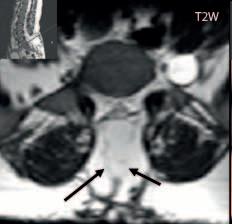

Prenatální sonografie: Spinální dysrafismus se obvykle diagnostikuje v 20.–22. týdnu, podezření může být vysloveno již v prvním screenigovém období (11.–13. týden). V screeningovém období 20.–22. týdne lze diagnostikovat Chiariho malformaci: je patrný příznak „banánu“ –

mozeček je posunut dorzálně a tvoří konvexní strukturu a příznak „citrónu“, který vytváří symetricky vkleslé části lebky frontálně.

Sestup mozečkových tonzil,

Myelomeningokéla

Obr. I.1.7e Myelomeningokéla již po operačním překrytí kožním krytem, Chiari II; stejný pacient jako na obr I 1 7c, d

Obr. I.1.7f Myelomeningokéla již po operačním překrytí kožním krytem, míšní nervy probíhají směrem ventrálním od nervové plakody (šipka), Chiari II; stejný pacient jako na obr I 1 7c, d, e

Obr. I.1.7g Šipky ukazují příznak citronu – vkleslé části lebky frontálně, Chiariho malformace, prenatální UZ (snímek zapůjčen z archivu prof MUDr P Caldy, CSc )

Obr. I.1.7h Příznak banánu (bíle označen) – mozeček posunut dorzálně, tvoří konvexní strukturu, Chiariho malformace, prenatální UZ (snímek zapůjčen z archivu prof MUDr P Caldy, CSc )

ch

Obr. I.1.7ch Otevřený spinální dysrafismus (defekt bíle označen), prenatální UZ (snímek zapůjčen z archivu prof MUDr P Caldy, CSc )